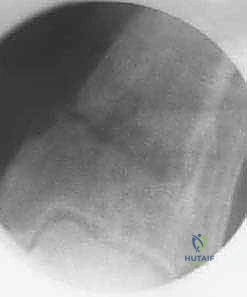

- الأشعة السينية الحاملة للوزن (Weight-bearing X-rays): وهي خطوة حاسمة. يجب أخذ صور الأشعة والمريض واقف، ليتمكن الدكتور هطيف من رسم المحاور الميكانيكية بدقة وحساب زاوية التشوه بالدرجات.

- الأشعة المقطعية (CT Scan): للحصول على صورة ثلاثية الأبعاد للعظام وتقييم مدى تآكل الغضروف وشكل التشوه بشكل أدق.

- الرنين المغناطيسي (MRI): يُطلب أحياناً لتقييم الأربطة والأوتار وحالة الغضروف المتبقي.